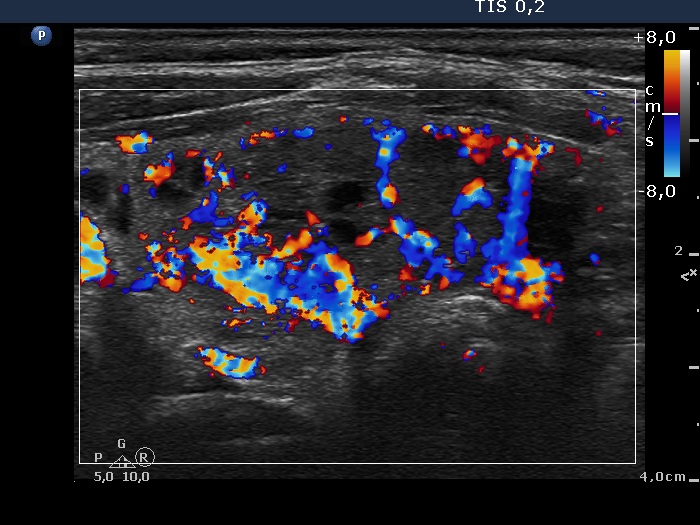

Ultrasonography. The thyroids were composed of multiple nodules with different echogenicities. The lesion presented various forms of intranodular hyperechogenic figures, including microcalcifications. Despite the presence of the latter, neither of the lesions were suspicious, they presented regular and sharp borders. increased intranodular blood flow.